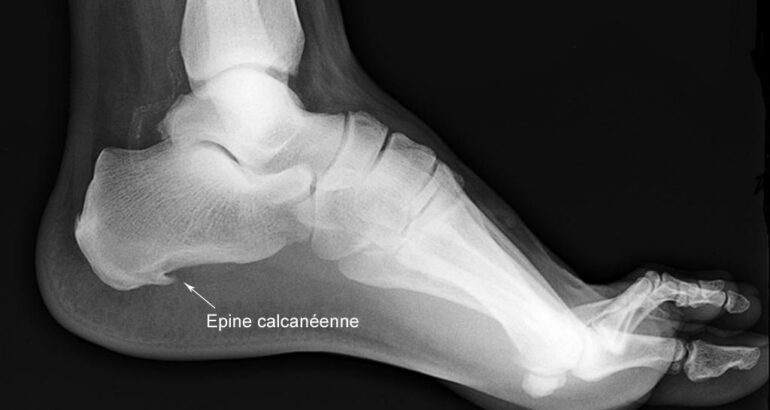

L’épine calcanéenne, ou épine de Lenoir, est une petite excroissance osseuse qui se forme sous l’os du talon. Elle est souvent liée à une inflammation de l’aponévrose plantaire, le tissu qui soutient la voûte du pied.

Le diagnostic repose principalement sur l’examen clinique, complété si besoin par une radiographie. Le surpoids, les chaussures inadaptées, les sports à impact et la station debout prolongée figurent parmi les principaux facteurs de risque.